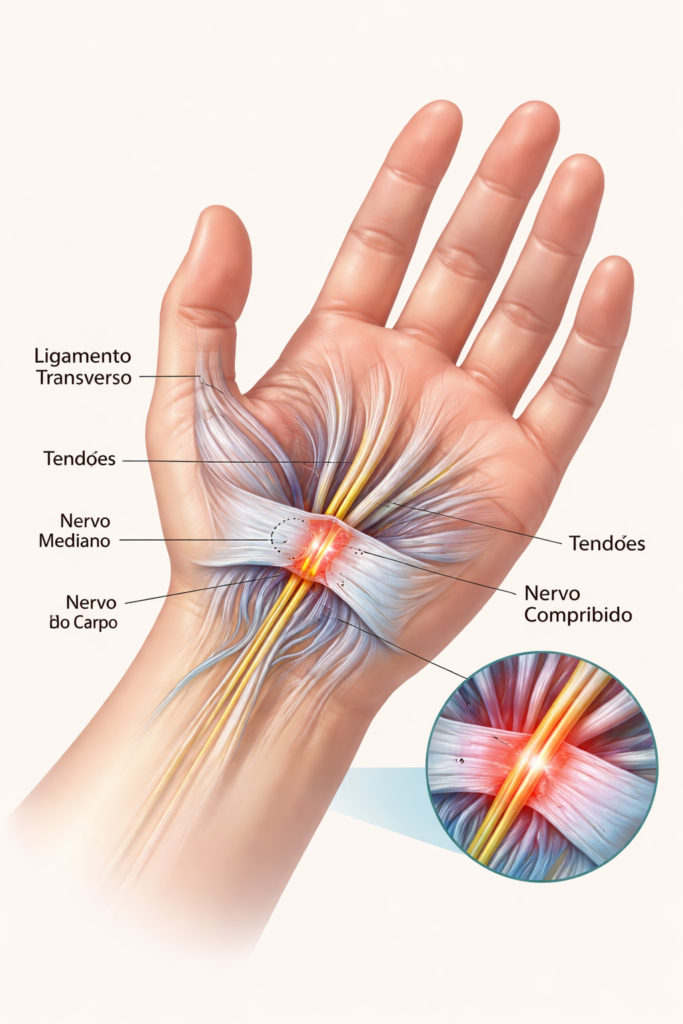

Cirurgia Endoscópica do Túnel do Carpo: Como Funciona e Por Que a Recuperação É Mais Rápida

Cirurgia endoscópica do túnel do carpo é uma técnica minimamente invasiva que utiliza uma microcâmera para liberar o nervo mediano através de uma incisão muito